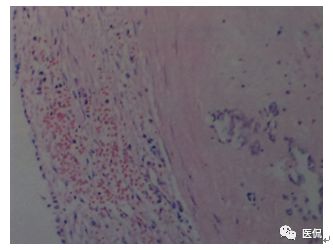

行全麻鼻内镜下唇龈沟双径路左上颌窦肿物摘除术。病理:鼻粘膜慢性活动性炎,间质广泛陈旧性出血,血肿形成、机化、钙化,纤维组织明显增生、包绕。

左上颌窦出血坏死性息肉。